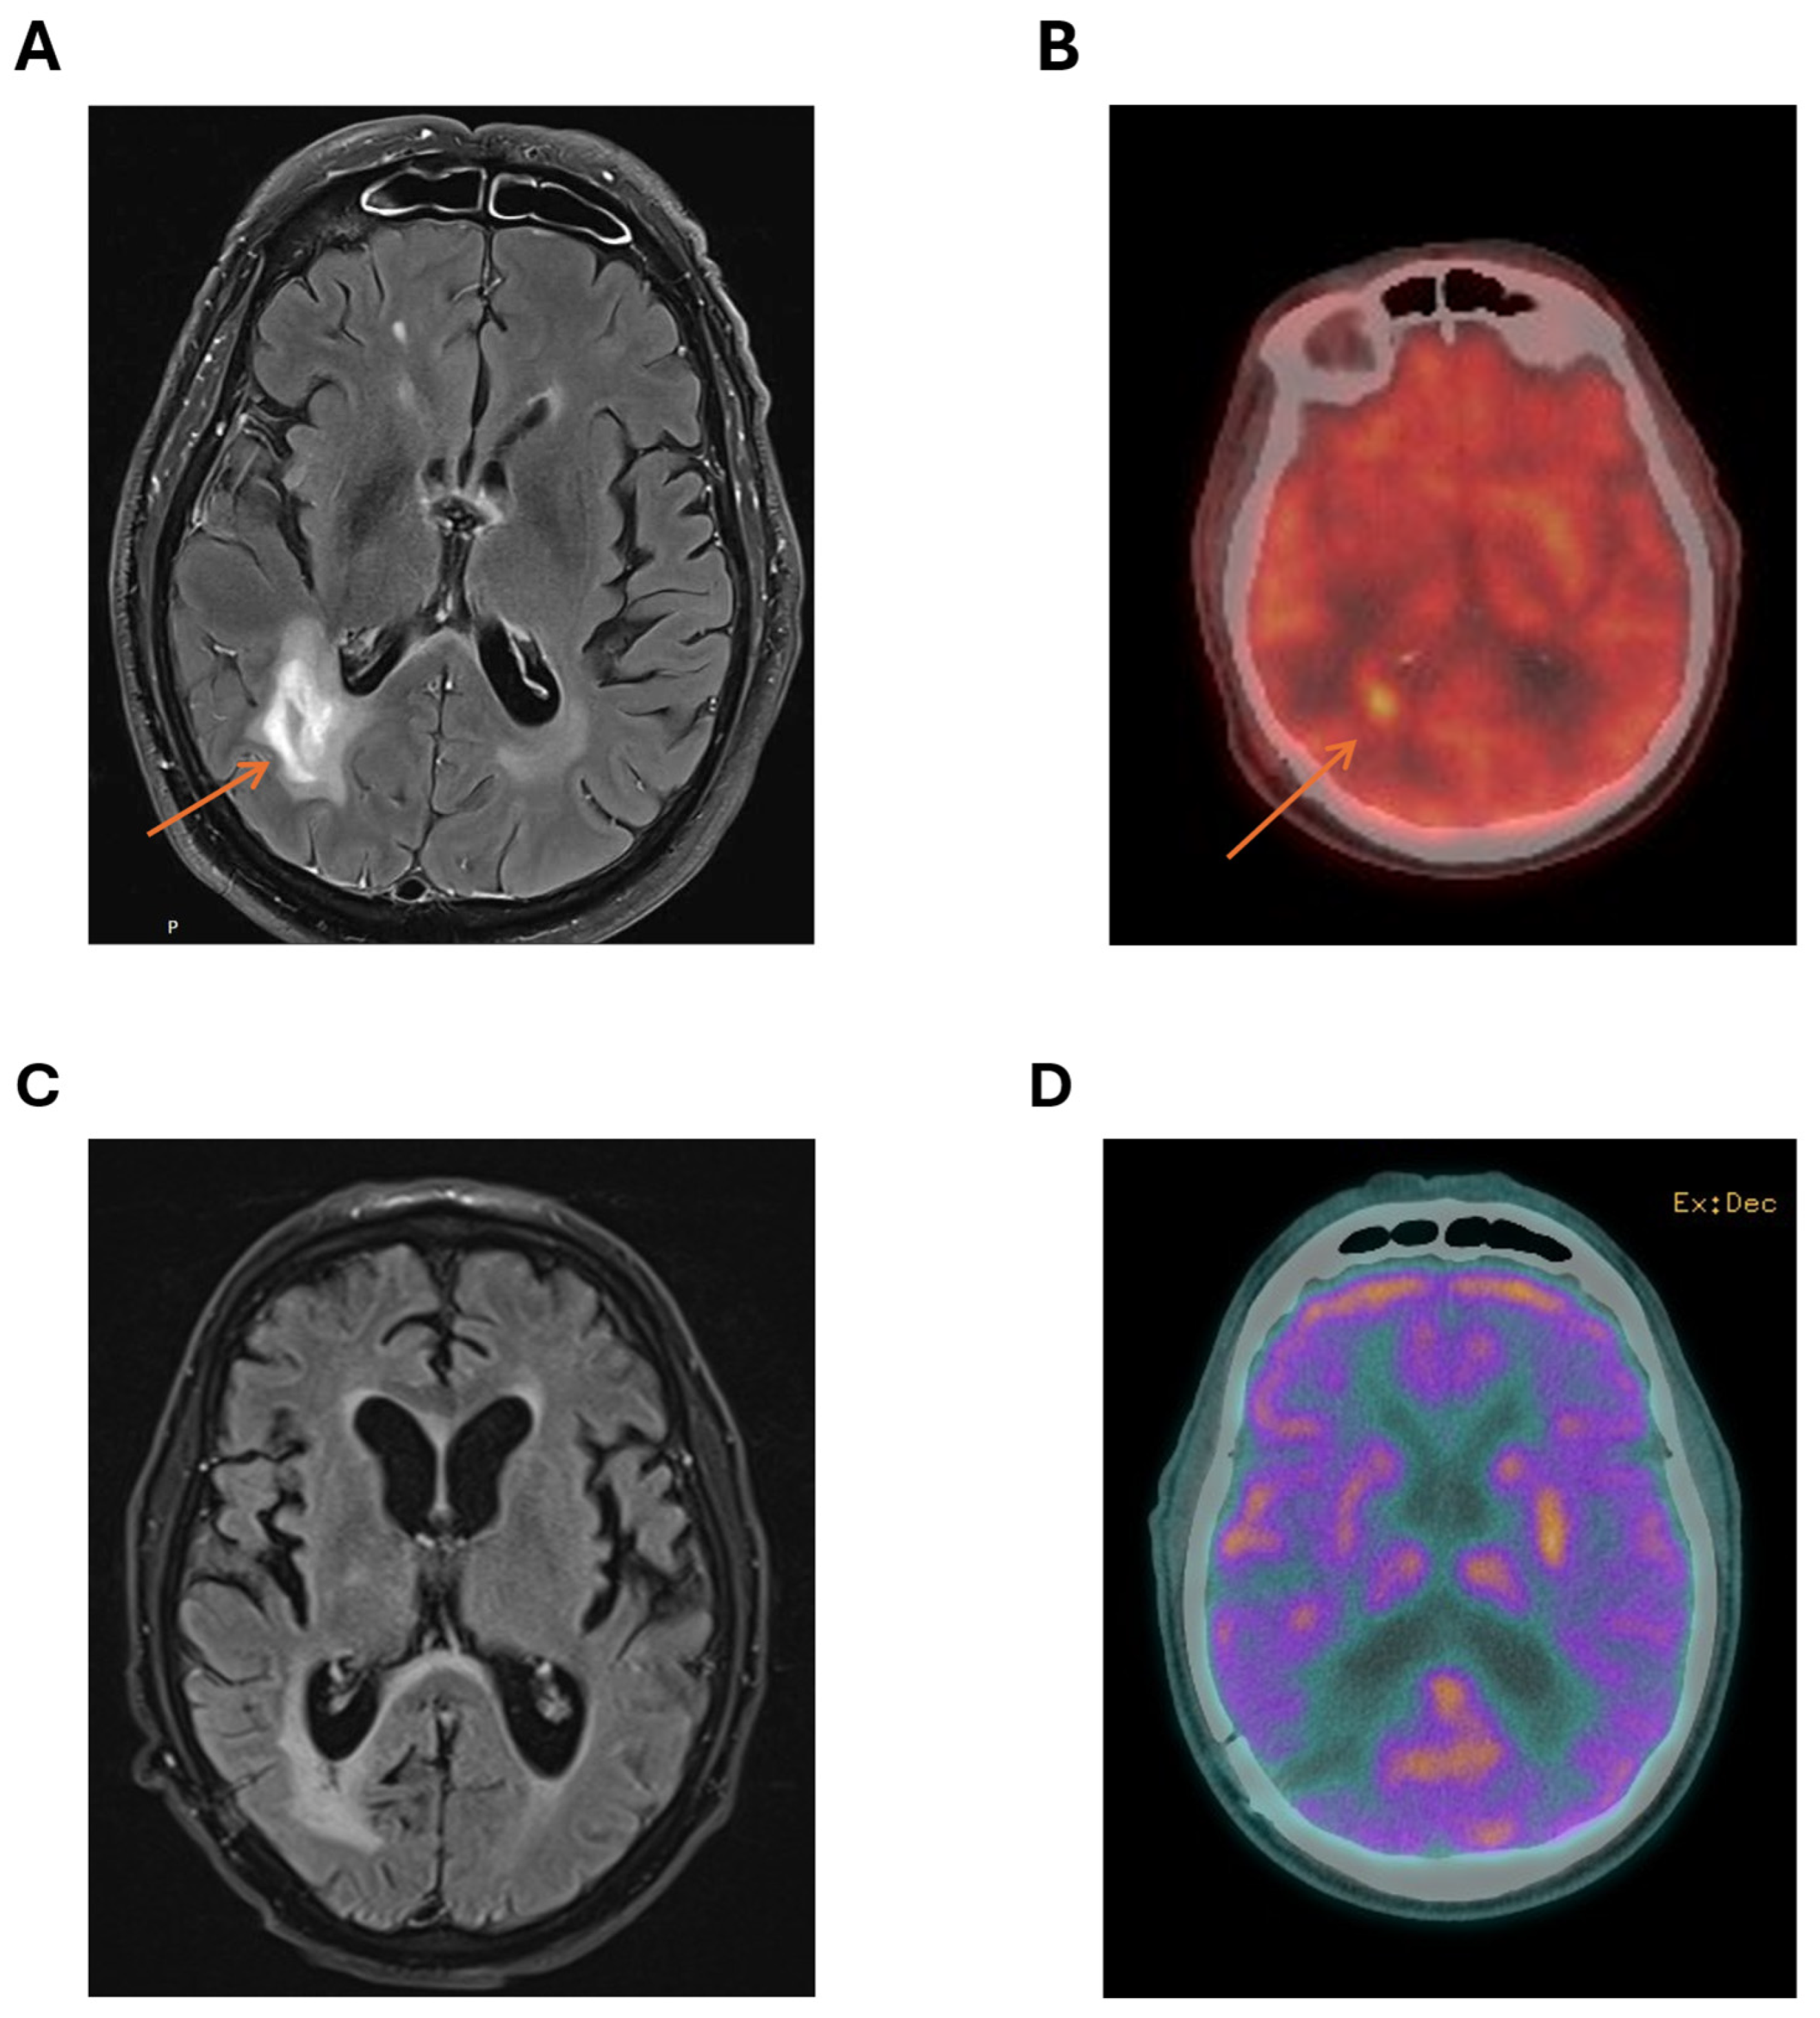

2. Case